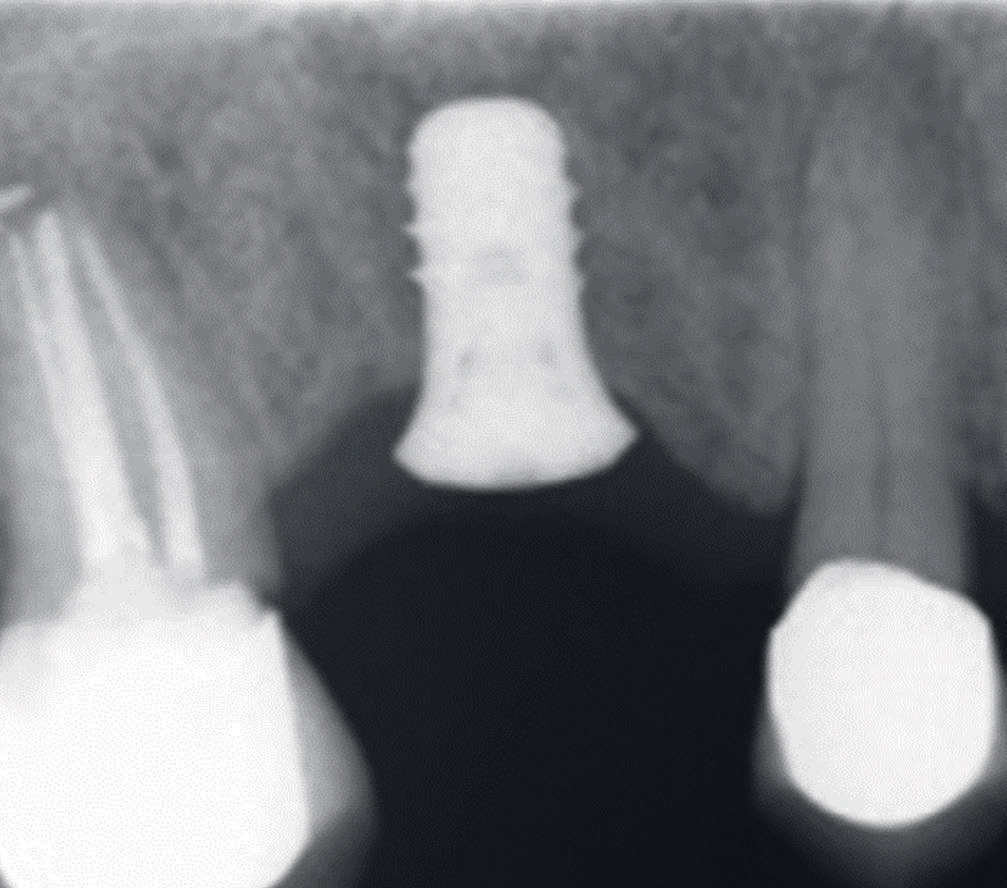

Behandling: i januar 2014 ble det innsatt et implantat, (ITI standard plus, «wide neck») med lengde 8.0 mm. Tilhelingen forløp uten komplikasjoner og røntgenbilde tatt 3 måneder senere indikerte osseointegrasjon av implantatet (figur 4). Det ble deretter tatt avtrykk og fremstilt en krone. Retensjonsskruen ble trukket til med 35Ncm. I tidsrommet april 2014 til april 2018 ble det ikke utført tannbehandling som endret okklusjonsforholdene i tannsettet. Etter 4 år i funksjon merket pasienten lette symptomer i implantatområdet og henvisende tannlege diagnostiserte svak mobilitet. Ved undersøkelse hos spesialist i periodonti april 2018 var det ikke mulig å måle lommer rundt implantatet og heller ikke påvise blødning ved sondering. Klinisk mobilitet grad I ble påvist i bucco-palatinal retning. Okklusal slitasje ble verifisert ved hjelp av blåpapir og overbelastning ble antydet som mulig årsak til implantatmobilitet. Pasienten ble forelagt to behandlingsalternativer: fjerne implantatet og eventuelt vurdere nytt implantat etter 12 ukers tilheling, eller forsøke å bevare implantatet etter først å ha fjernet kronerestaurering og så observere om implantatet re-osseointegrerte. Pasienten valgte det siste alternativet. Kronen ble fjernet og submucosal tilhelingstopp montert (figur 5).

Figur 4. Røntgenbilde fra april 2014 indikerer osseointegrasjon av implantat regio 16.